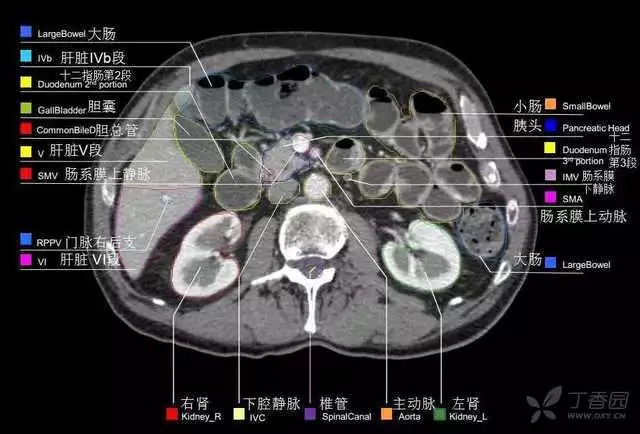

腹部肝脏高清CT断层的图谱

全腹部高清CT图谱,淋巴结彩色图谱,血管解剖图谱大汇总!

超声肝脏分叶及分段

肝脏分段和基本解剖学标志